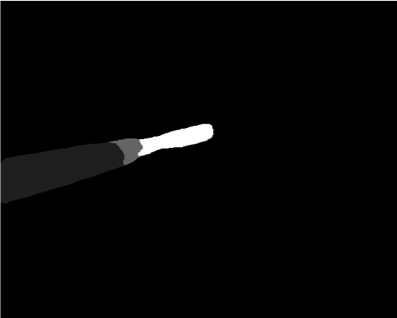

Our challenge was made up of 3 sub-problems. The first was binary instrument segmentation, where each frame was separated into da Vinci Xi instruments and a background class, which contained an ultrasound probe, surgical clips and porcine tissues. The second task was instrument part segmentation, where we scored the participants on whether they could correctly segment each articulating part of the instrument (see Fig. 3). Our final task was to segment and classify the instruments (see Fig. 4).

We provided the first 225 frames of 8 sequences as training data and kept the last 75 frames of those 8 sequences as test data. 2 of the full 300 frame sequences were kept as test sequences. Test labels were kept hidden from the participants. Our datasets contain 7 different robotic surgical instruments. The Large Needle Driver, Prograsp Forceps, Monopolar Curved Scissors, Cadiere Forceps, Bipolar Forceps, Vessel Sealer and additionally a drop-in ultrasound probe, which is typically held in the jaws of the Prograsp Forceps instrument. Samples from the training datasets are depicted in Fig. 2 and examples of the different instrument types are shown in Figure 3 and 4.

Our labelling was performed by a dedicated segmentation team at Intuitive Surgical using the open source software Viame333https://github.com/Kitware/VIAME which provides functionality for frame-by-frame polygon creation. We labelled only the left eye in the stereo pair to reduce labelling time. Labels were provided on an instance level with separate annotated images per object.